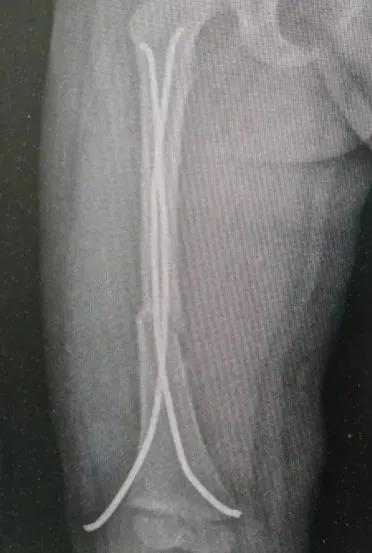

近日景谷县人民医院外二科收住两名患儿,其中一名:李xx,7岁,因摔伤左小腿后疼痛、活动受限3小时收入,入院后完善相关检查,明确诊断为左胫骨中下段螺旋性骨折。另一名患儿:胡xx,3岁,因摔伤右大腿后疼痛、活动受限8小时收入,入院后完善相关检查,明确诊断为右股骨中段骨折。

景谷县人民医院骨科接诊两位患者后,分别结合患儿的年龄、相关检查资料做了综合评估、讨论,征得家属同意后,精心制定了手术方案,为两名患儿成功完成了弹性髓内钉的微创治疗。